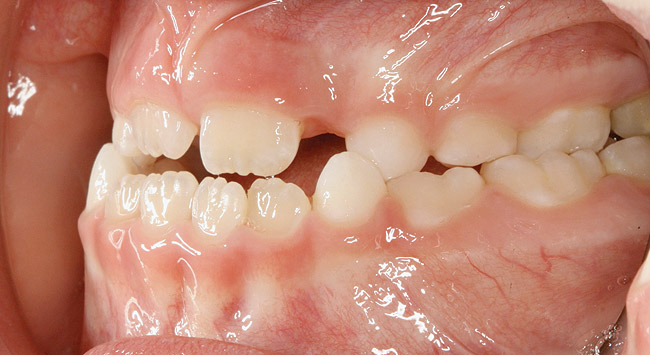

(14.) Angle Class III occlusion with constricted maxilla.

Figure 14

(15.) Cephalometric evaluation demonstrates significant tonsillar blockage of the airway and bimaxillary retursion.

Figure 15